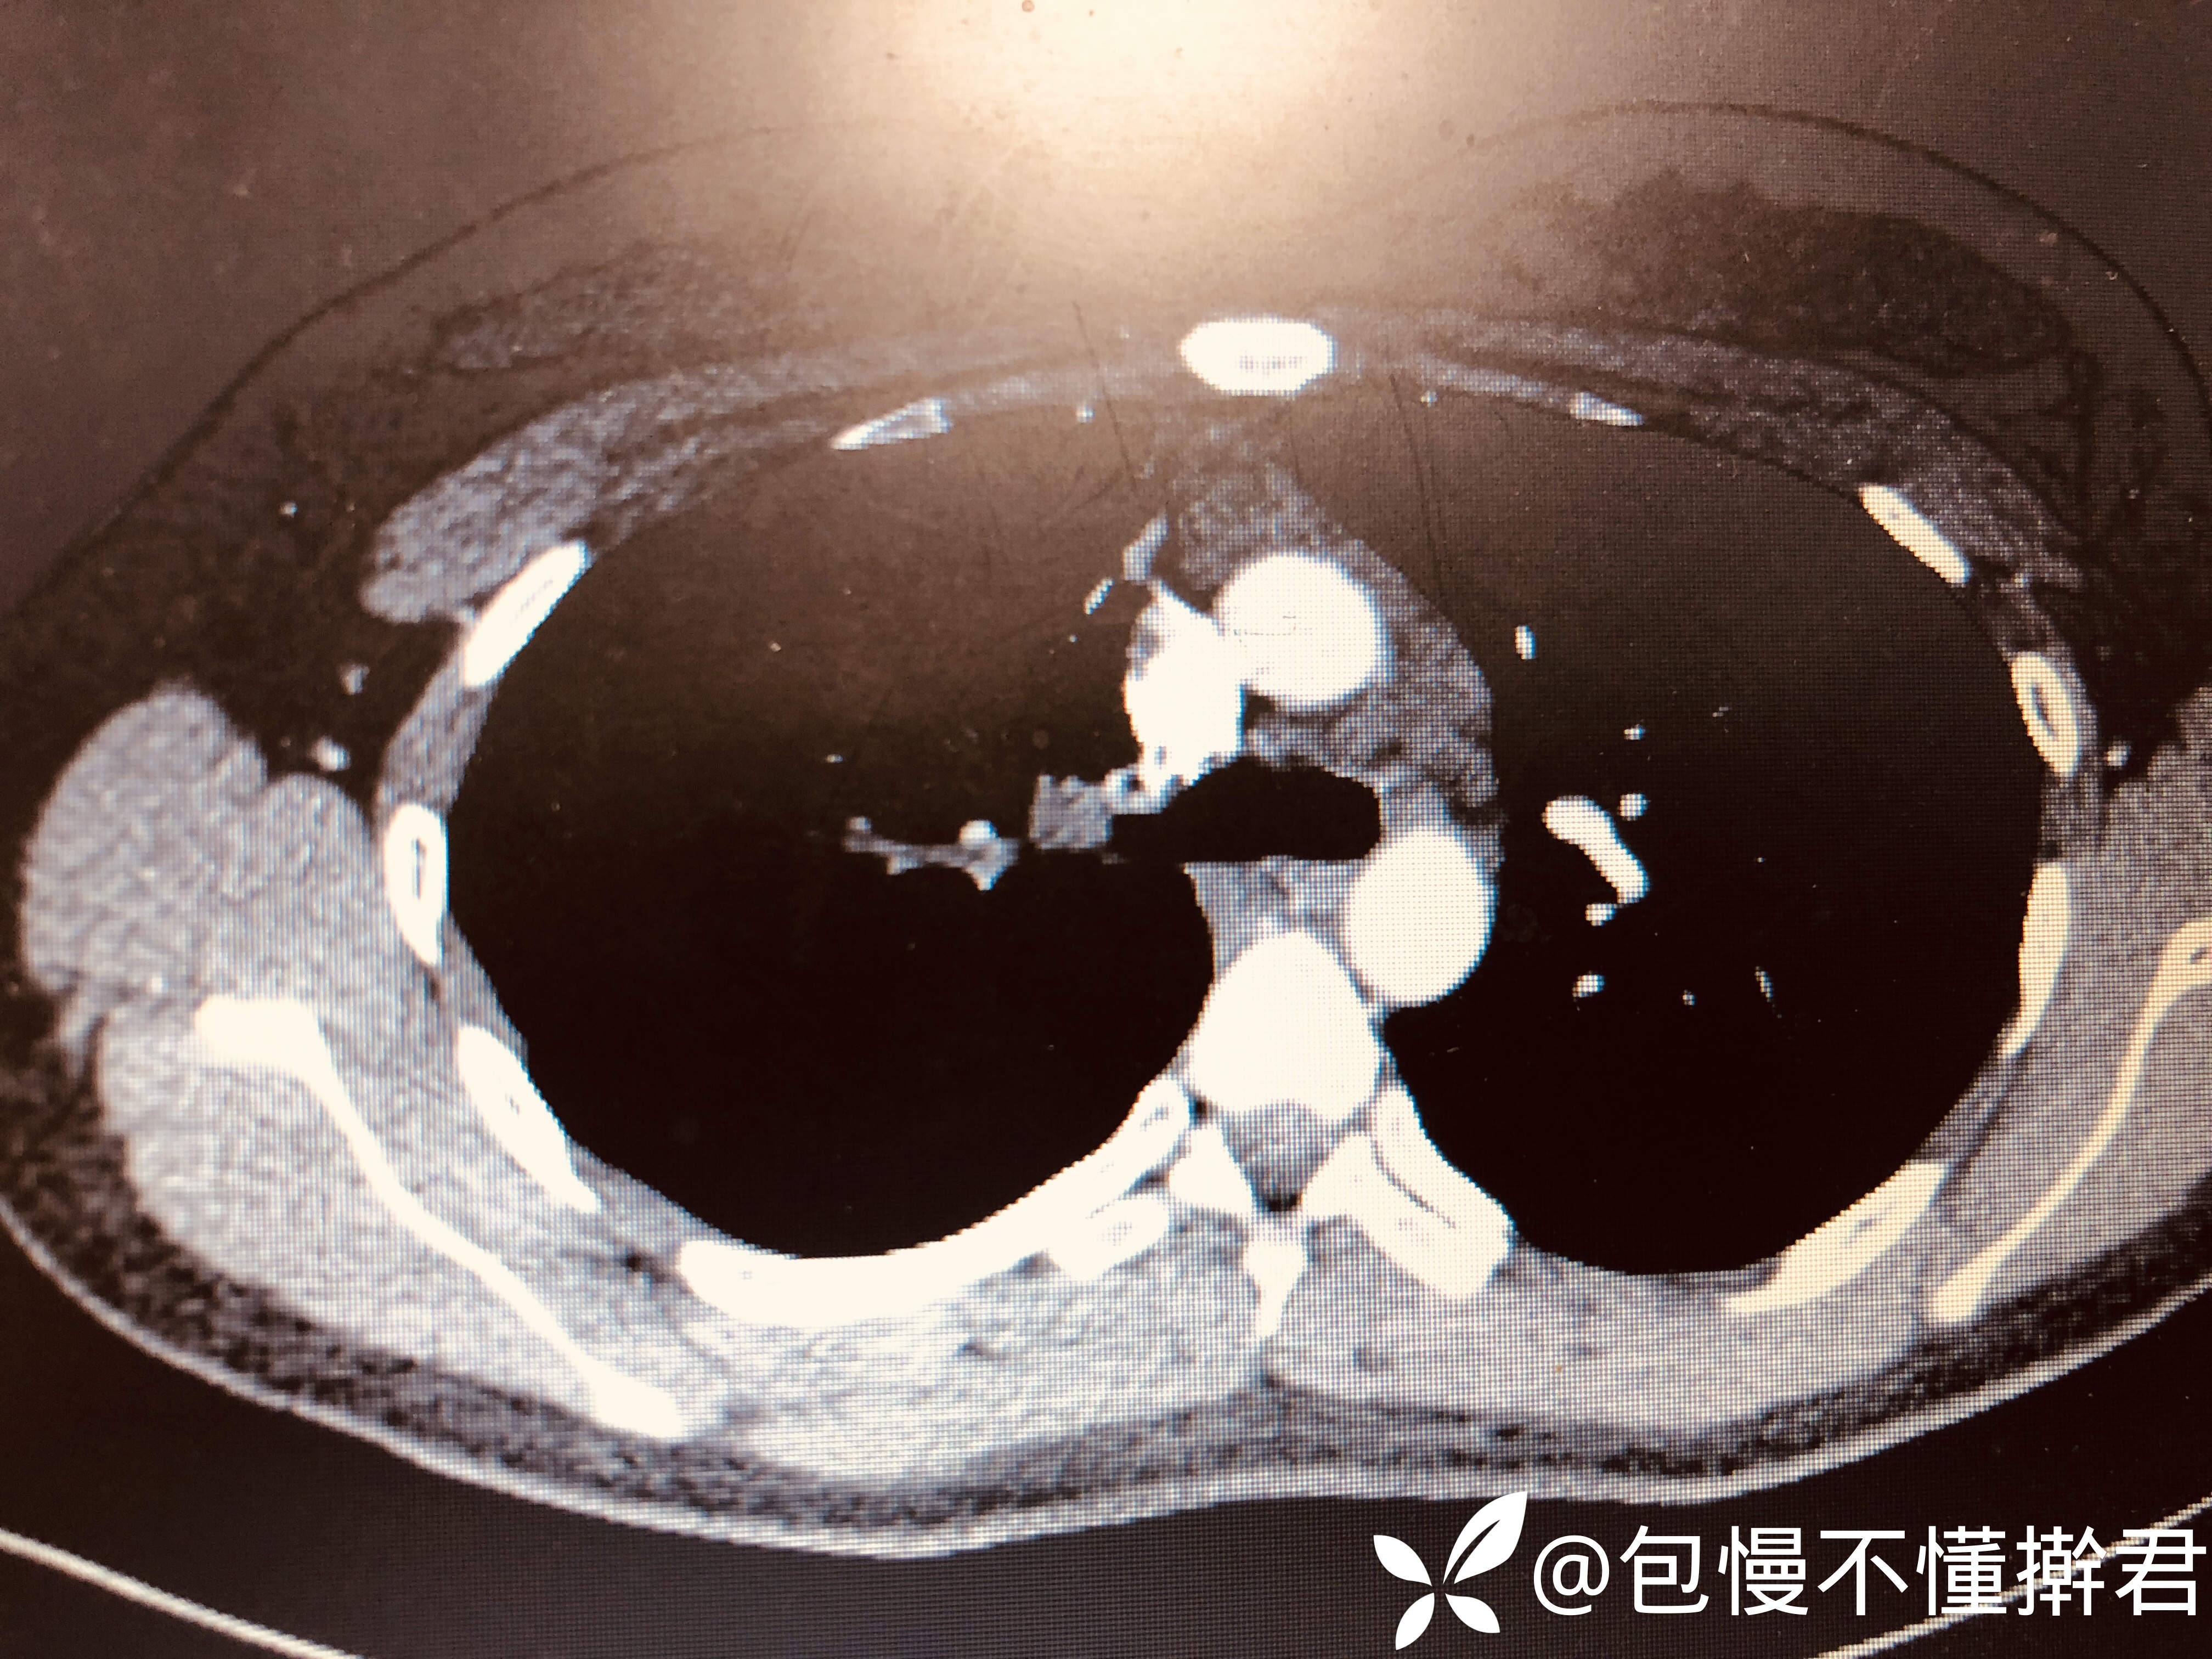

主诉:体检发现右上肺占位5天

简要病史:5天前因入学体检就诊当地医院行胸片右肺上叶不张,无呼吸系统症状

增强CT:

临床诊断:右上肺占位待查